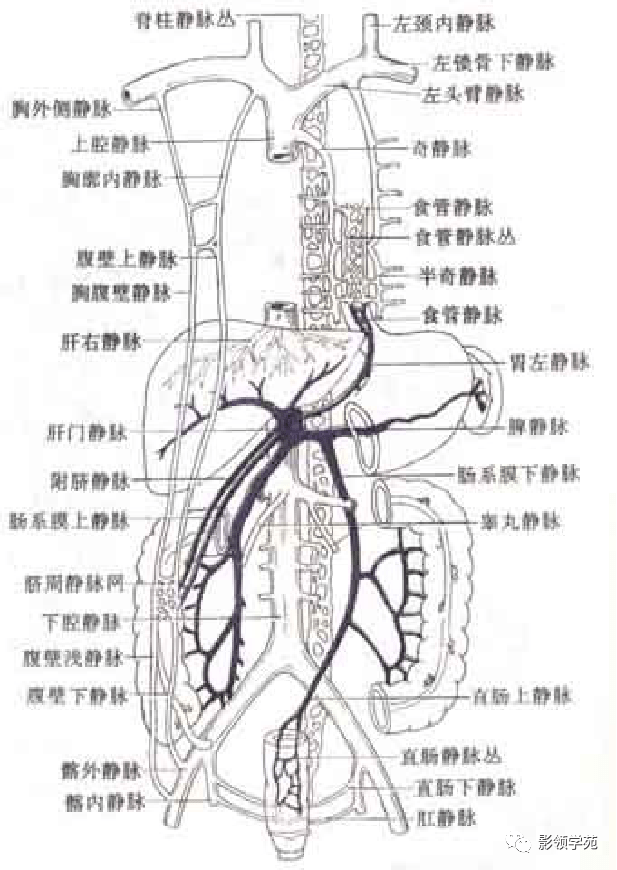

腹部动静脉

腹部动静脉